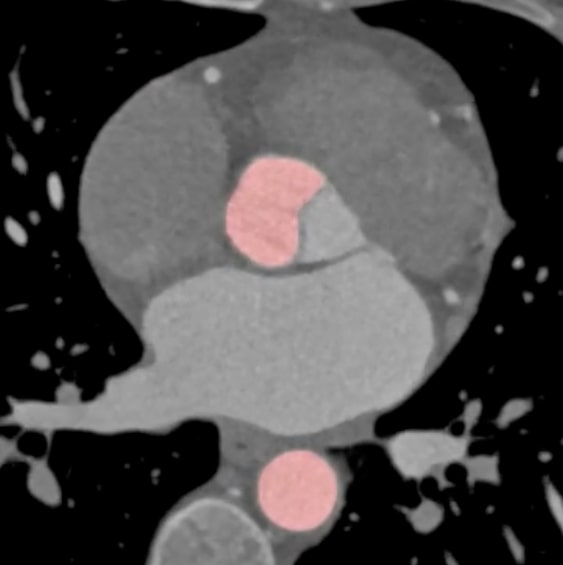

Contrast-enhanced CT images are the preferred method for the assessment of thoracic aorta including visualization of pathologies (e.g. aortic aneurysm*) and measurement of diameters at specific levels. Moreover, accurate segmentation and visualization of aortic root is of special interest in cardiac CT imaging. Aortic root is the proximal portion of ascending aorta beginning at the level of aortic annulus and extending to sinotubular junction. Between each commissure of the aortic valve there are usually three aortic sinuses.

Automatic detection of the aortic root is an important element for further AI data processing. The difficulty in automatically segmenting the aortic root is twofold. Firstly, the aortic valve is poorly visible and classical methods of segmentation based on thresholding usually fail. Secondly, the valve can be opened and then the contrast connects directly to the left ventricle. In both cases, radiologists and cardiologists can rely on the general anatomical features of aortic sinuses/aortic annulus to extrapolate the location of a poorly visible aortic valve. The challenge is to create an algorithm that incorporates this intuition and correctly segments the aortic root in both cases.

ML generated segmentation of thoracic aorta. Note the accurate segmentation of aortic cusps.